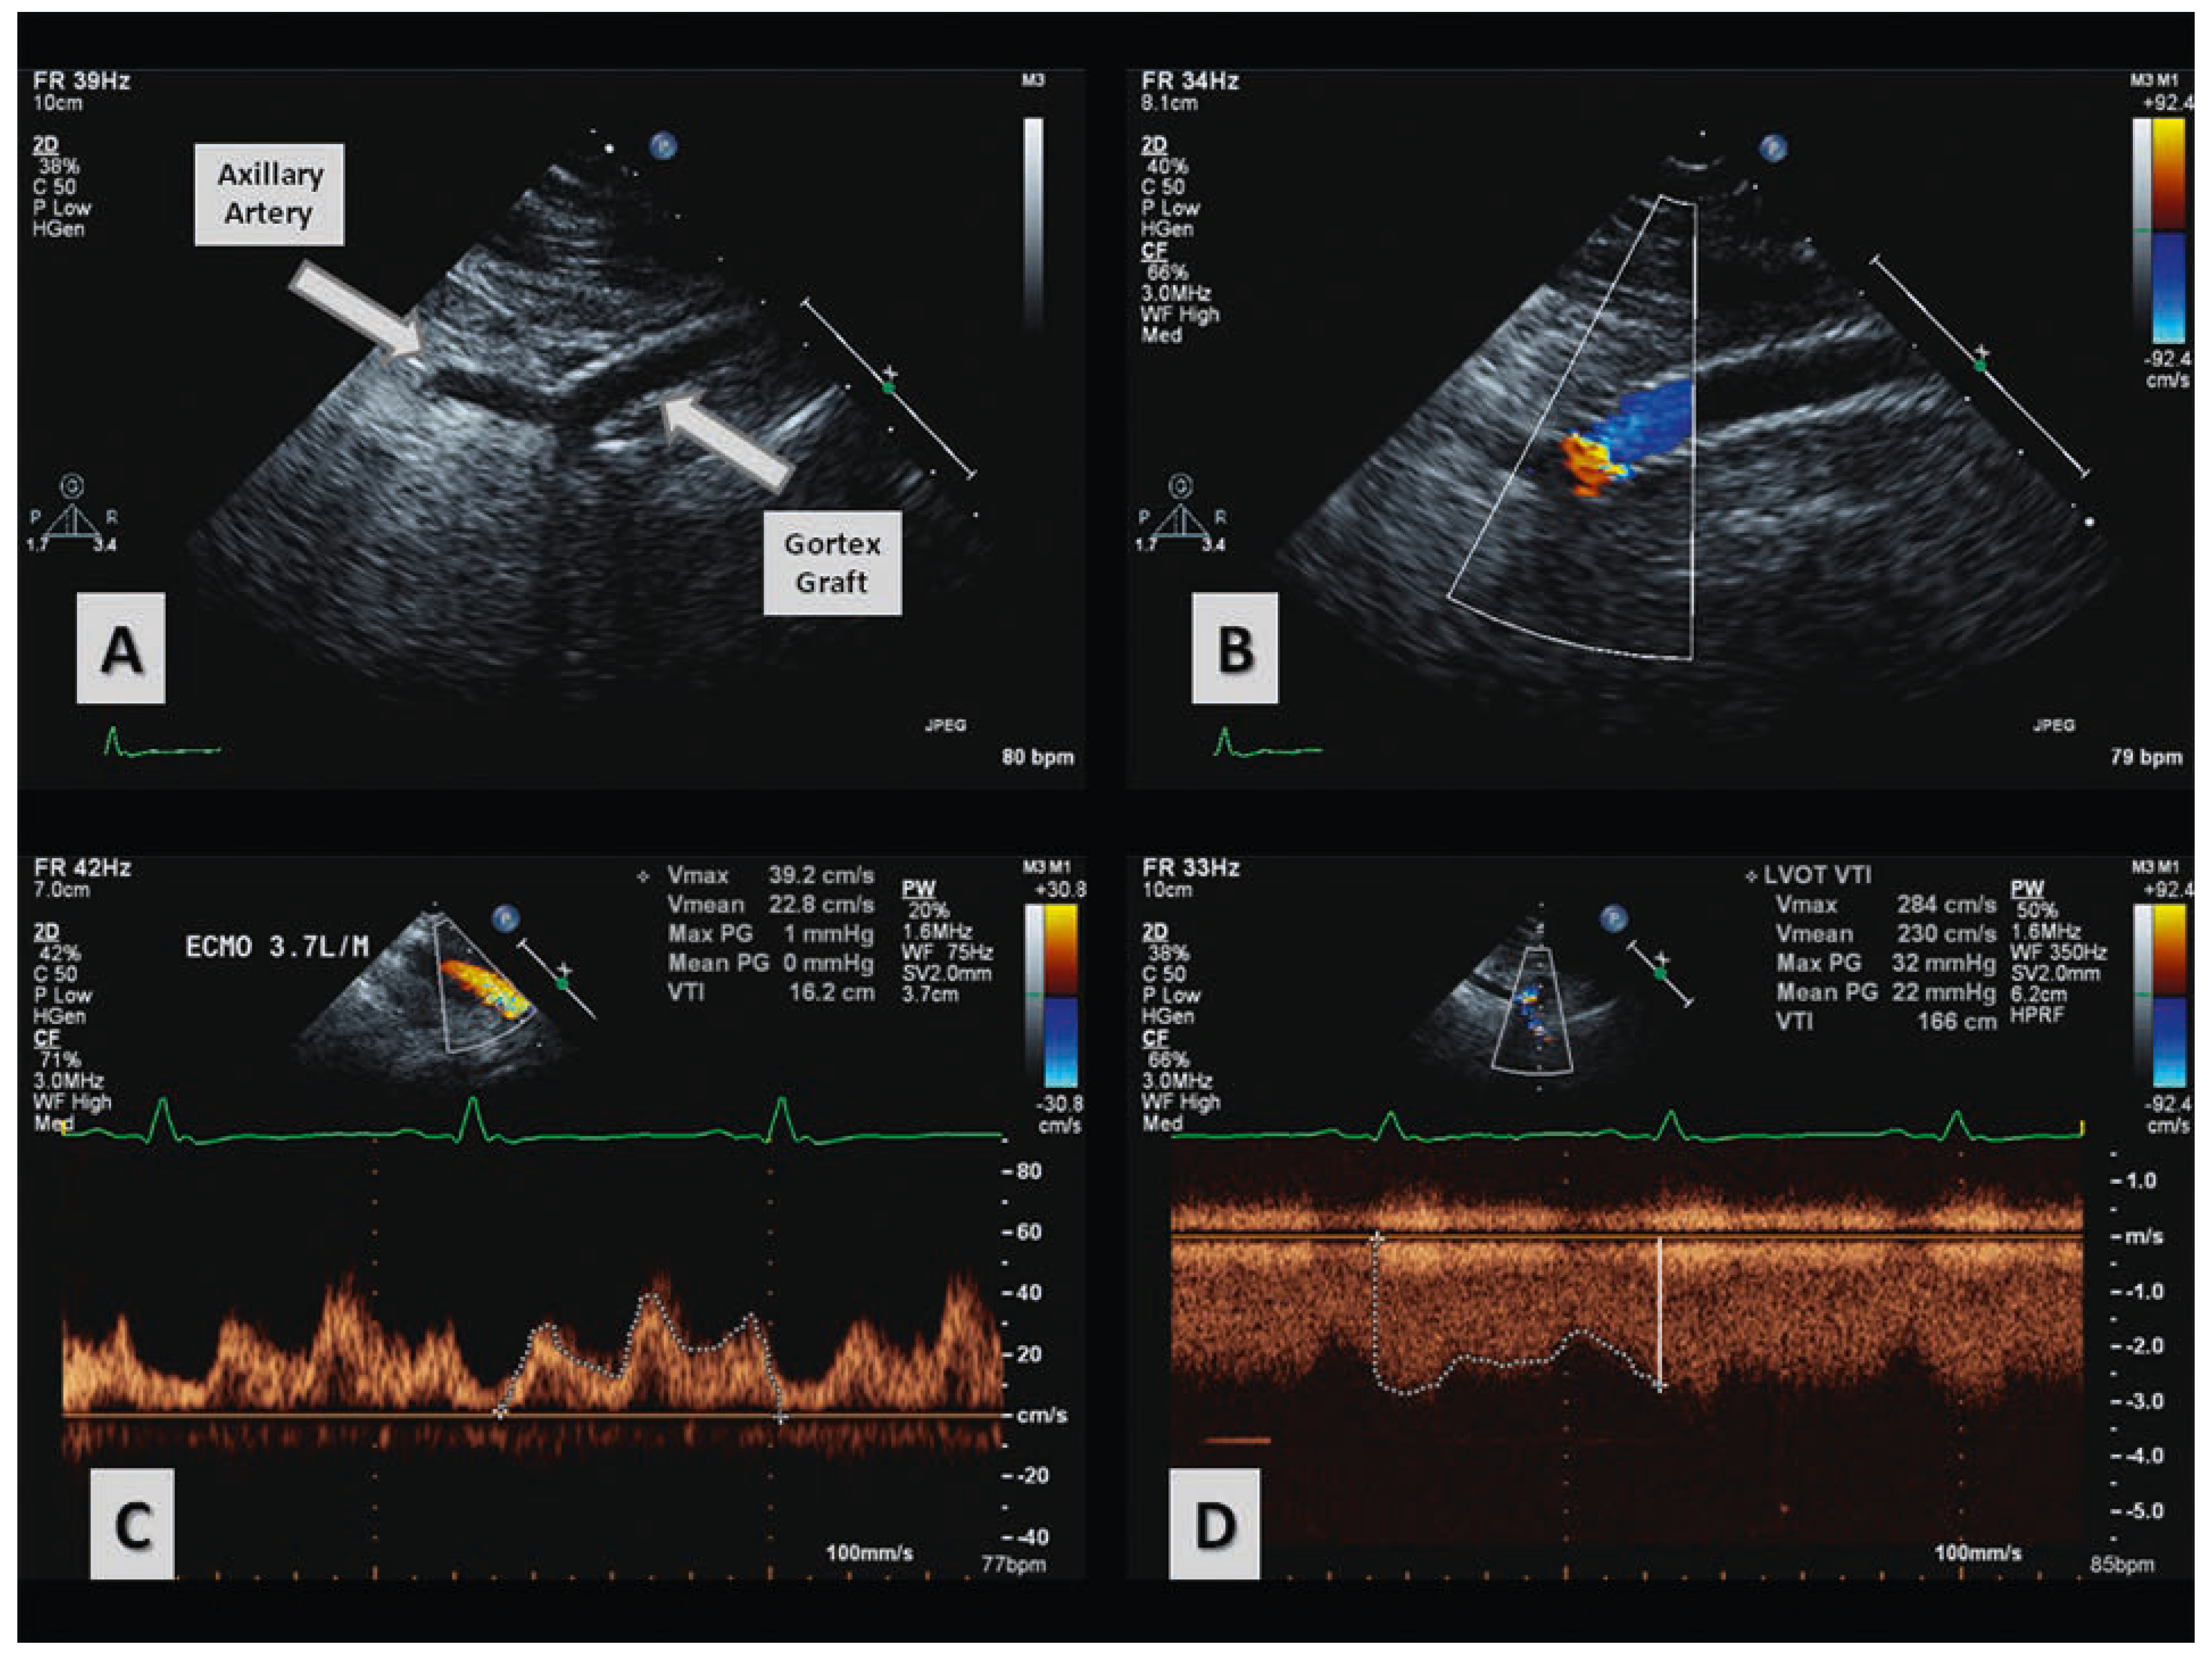

Quantification of Differential ECMO Return Flow Through an Axillary Artery Anastomosis Graft with Spectral Doppler Echocardiographyphy

Case report